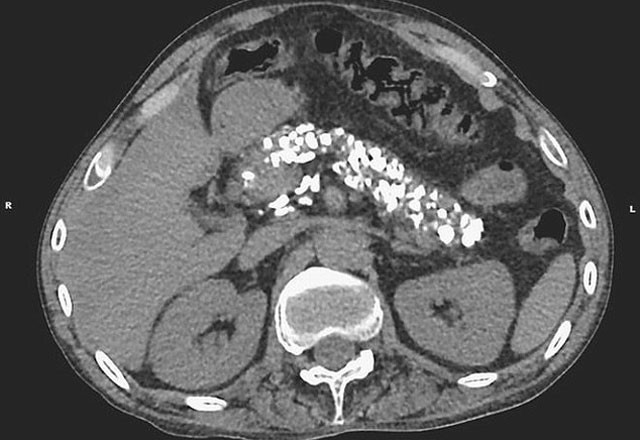

Sonuçlar, kronik pankreatiti işaret ediyordu. Aşırı alkol tüketimi, adamın pankreasındaki bazı dokuların sertleşmesine yol açmıştı. Kireçlenme olarak bilinen bu durum, tedavi edilemeyecek hale gelmişti.

Adamın pakreasındaki tortular, New England Journal of Medicine'de yayınlanan röntgende de görülüyor. Uzmanlar aşırı alkol tüketiminin zararlarını görmek için adamın semptomlarına bakmanın yeterli olacağını söyledi.